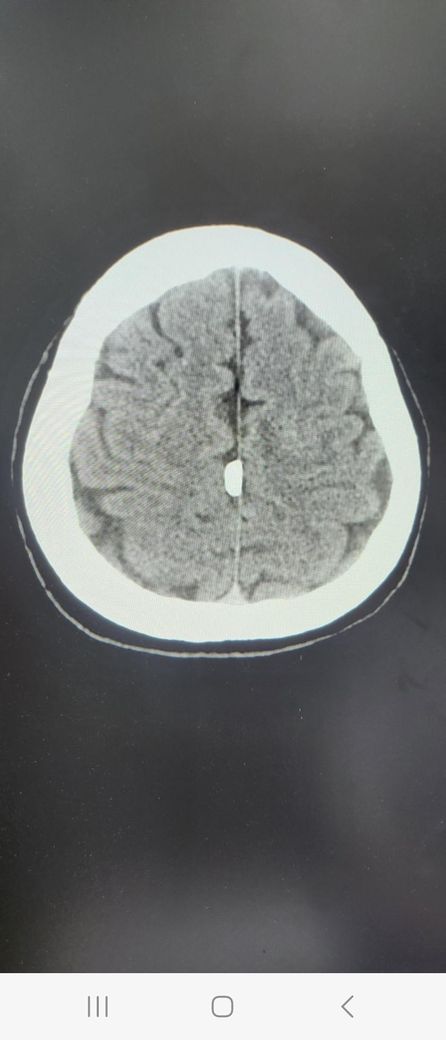

병원에서 궁금하면 종양인지 석회인지 mri찍어볼래요?라는데 환자 증세가지고 홀짝하는것도 아니고.... 전문가 선생님들 도와주세요

환자의 증세를 가지고 홀짝을 하는 것이 아니라 해당 CT 소견을 통해서는 단순한 석회인지 아니면 종양인지에 대한 감별이 가능하지 않기 때문에 확인을 위해서는 MRI 등의 더 정밀한 검사가 필요한 것이 맞습니다.